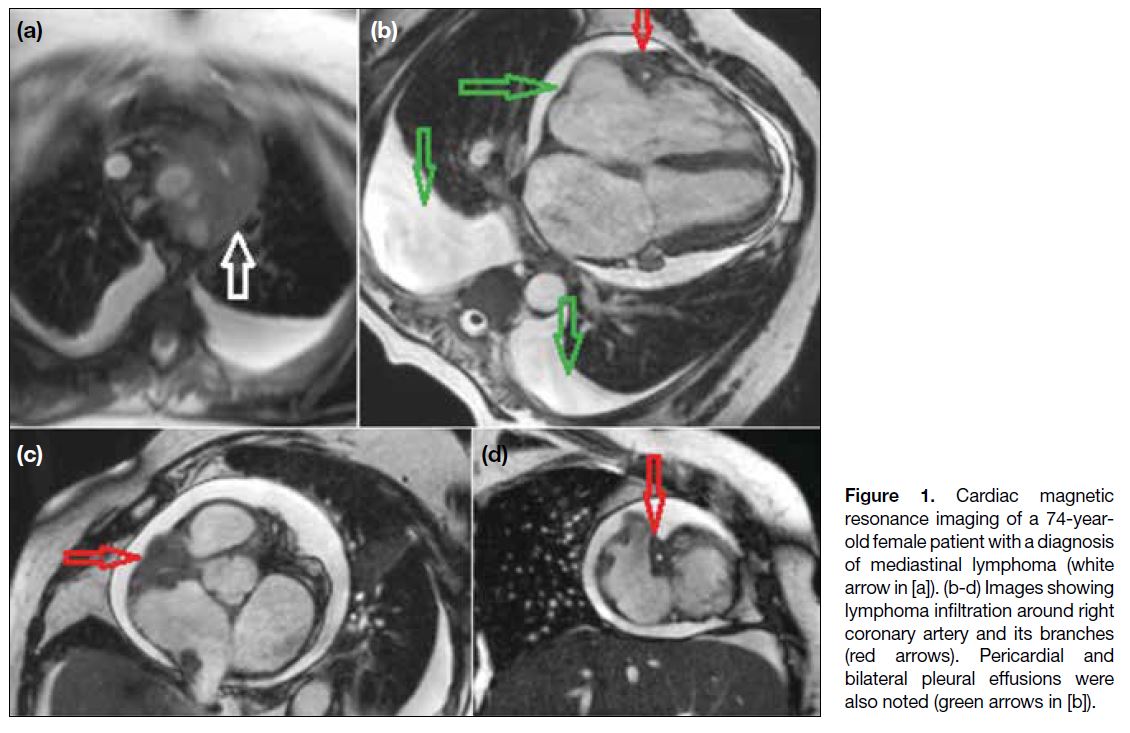

Figure 1 depicts metastatic involvement of pericardial

fat surrounding the right coronary artery from a

mediastinal lymphoma. Lymphatic drainage of the

pericardial space is by lymphatic channels located in

the pericardium that converge at the root of the aorta,

where these channels are most often obstructed, giving

rise to pericardial effusion.[8] Figure 2 shows an example

of pericardial metastasis from renal cell carcinoma.

Figure 1. Cardiac magnetic

resonance imaging of a 74-year-old female patient with a diagnosis of mediastinal lymphoma (white arrow in [a]). (b-d) Images showing lymphoma infiltration around right coronary artery and its branches (red arrows). Pericardial and bilateral pleural effusions were also noted (green arrows in [b]).